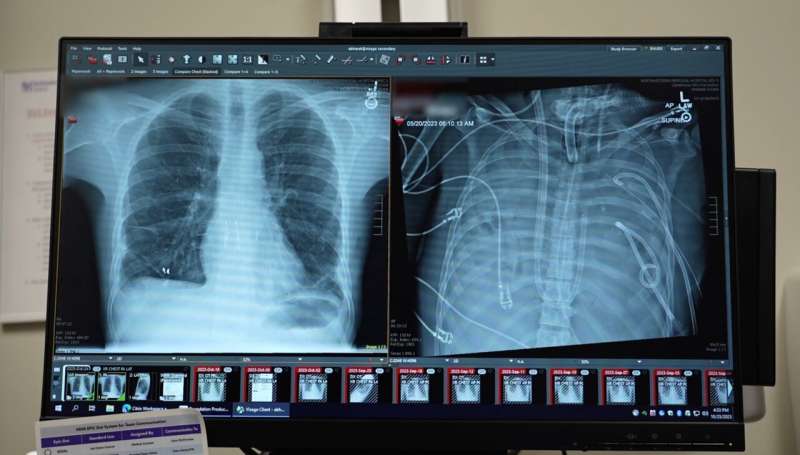

Reporting in the journal Med, surgeons describe how they removed a patient’s infected lungs and built “artificial lungs” to keep him alive until a double lung transplantation was available. The work shows how the approach may serve as a life-saving bridge to transplantation.

The patient, a 33-year-old man, developed acute respiratory distress syndrome (ARDS), a life-threatening condition in which inflammation and infection overwhelm the lungs. Triggered by the flu, his lungs deteriorated rapidly and were further compromised by bacterial pneumonia. Eventually, his lungs, heart, and kidneys started to fail. A double lung transplant became his only chance of survival.